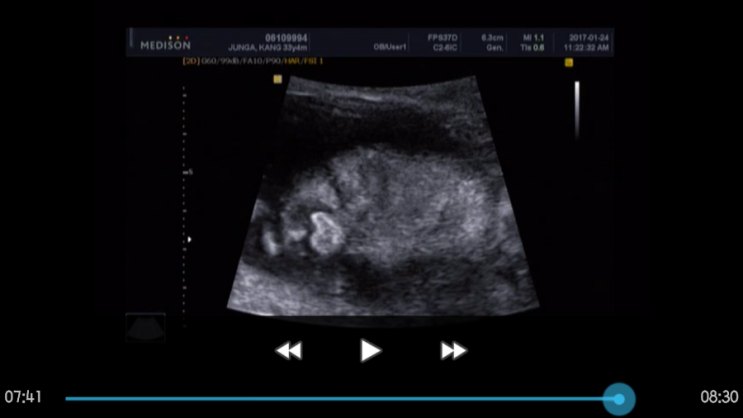

[임신23주] 경부길이, 따봉이얼굴, 일상

오늘로 임신 23주3일.어플상 D-116일 따봉이와 함께하고있는 요즘.비록 다른 산모들처럼 여행도 다니고 산...